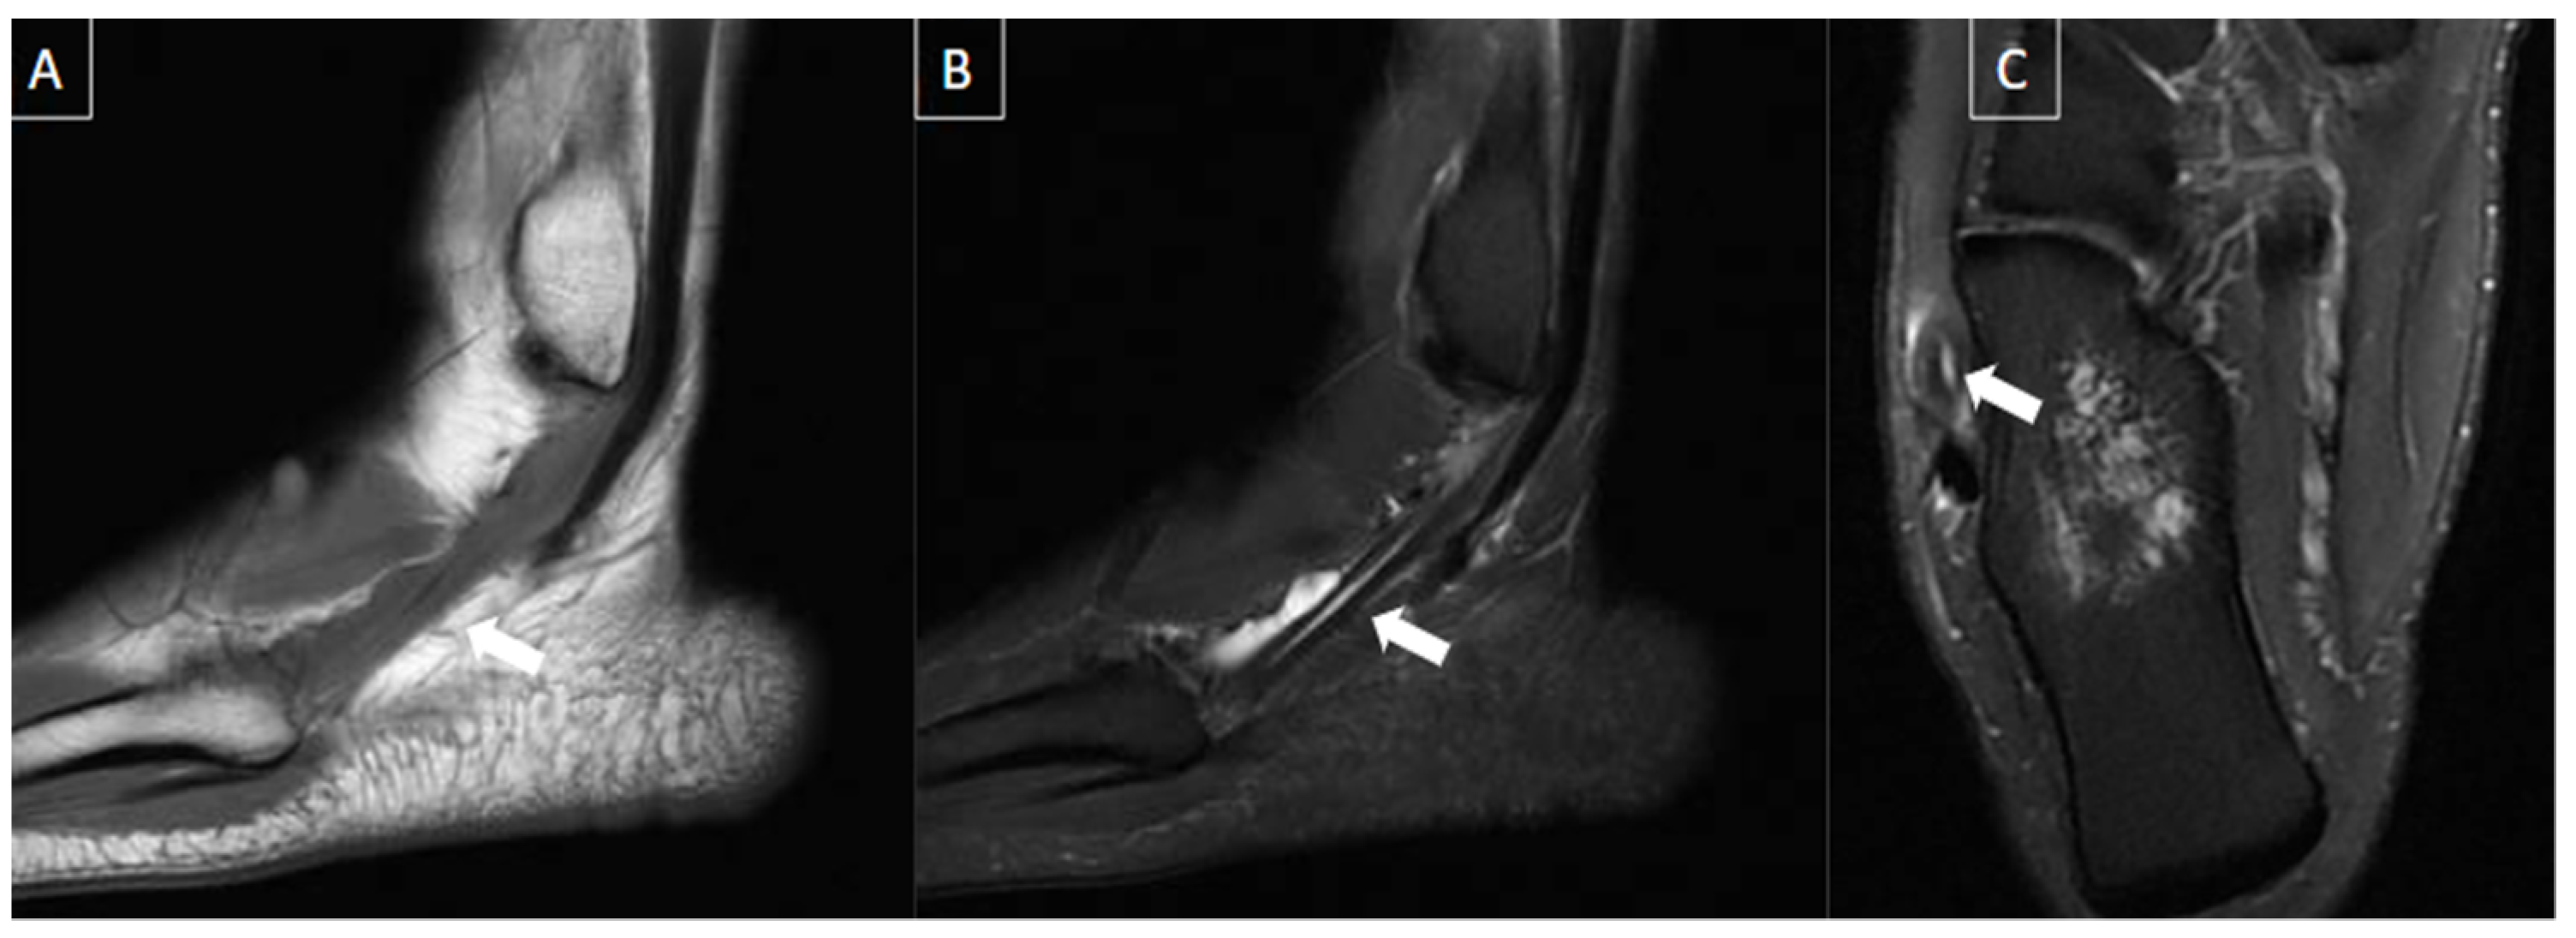

6.6. Tendon Pathologies

| Tendon pathologies | Varies according to the cause (tendinosis/ tendinopathy, tenosynovitis, and peritendinitis). | Intra and peritendinous alterations with enlargement of the tendon and various degrees of hypoechogenicity. | Enlargement and signal abnormalities in the affected tendon. High signal intensity can be seen involving the tendon and peritendinous soft tissues. |